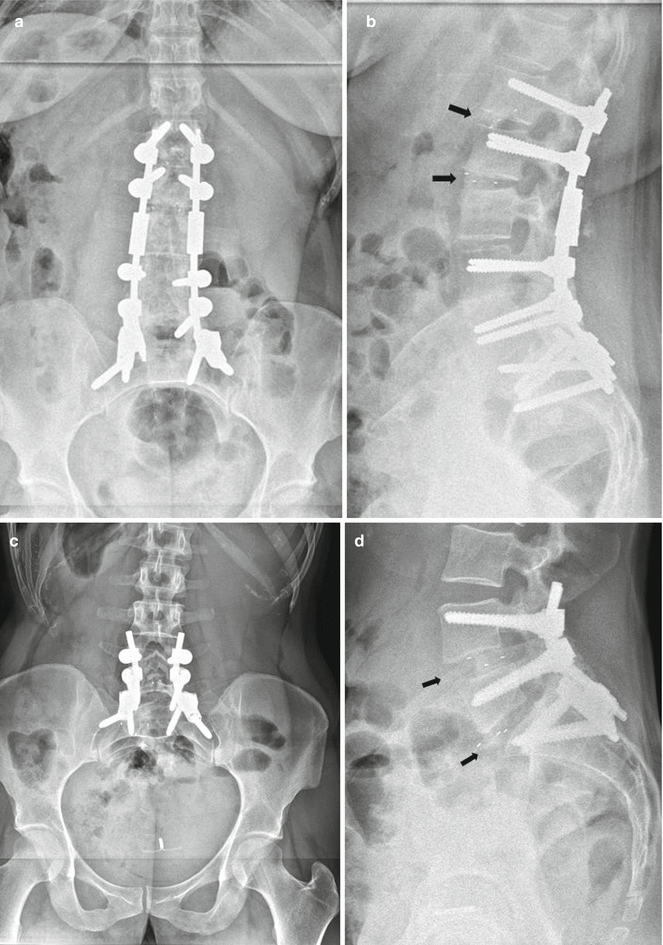

Oblique Lumbar Interbody Fusion Musculoskeletal Key What Is Lumbar Spine With Obliques Lumbar spine oblique radiology tutorial. Basic radiographic spinal anatomy tutorial.more. This area includes the lumbar region and the sacrum. The lumbar spine series is comprised of two standard projections along with a range of additional projections depending on clinical. It is easier to centre to the spine when surface anatomy landmarks provide a. Correct 45° patient rotation results in the. What Is Lumbar Spine With Obliques.